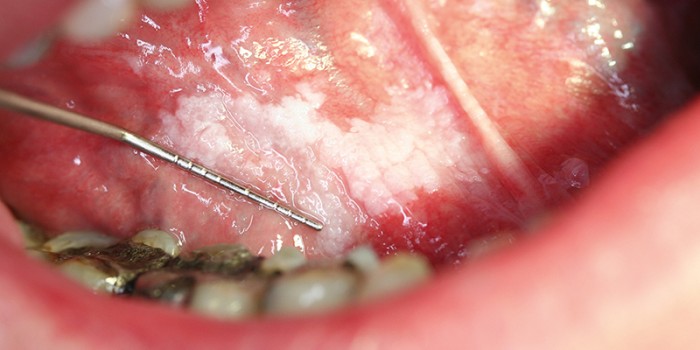

De patiënte bemerkte een witte verkleuring van de tong (leukoplakie) [figuur 1]. Deze premaligne afwijking ontaardt bij 24% van de gevallen in een maligniteit.6 Patiënten met een tongcarcinoom hebben vaak een zwelling of ulcus in de tong [figuur 2]. Aanvankelijk is deze asymptomatisch, maar bij doorgroei ontstaan pijnklachten en mobiliteitsverlies van de tong, waardoor spraak- en slikproblemen kunnen optreden. De pijn kan uitstralen naar de kaak, hals en oren. Bij onderzoek van de tong wijst een geïndureerde zwelling op een maligniteit. Verder let de huisarts op lymfadenopathie van de hals, vooral submandibulair en dorsaal van het kaakkopje. Een biopt van de laesie kan de diagnose bevestigen.

De aios in de casus stelde de werkdiagnose fibroom, een afwijking die veroorzaakt wordt door chronische irritatie van onder andere bijten of een slecht passende gebitsprothese. Een fibroom zit echter meestal op het wangslijmvlies of op de tongpunt, maar kan zich soms ook presenteren op de laterale tongrand. Een andere benigne tumor van de mondholte is het papilloom, een wratachtige afwijking veroorzaakt door het HPV-virus. Noch het fibroom, noch het papilloom geeft doorgaans pijnklachten en beide groeien exofytisch, in tegenstelling tot het tongcarcinoom [figuur 3].